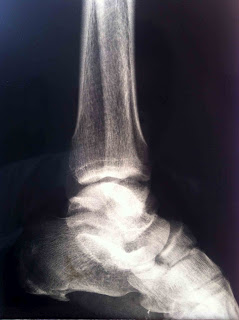

Cuenta con radiografias AP y lateral de tobillo izquierdo, dorsolateral

y oblicua de pie izquierdo donde se observa solución de continuidad osea e

incongruencia articular a nivel de la articulación de lisfranc con

desplazamieto hacia lateral, se observa perdida de la continuidad osea a nivel

de escafoides y cuboides y en falange proximal del quinto rayo.